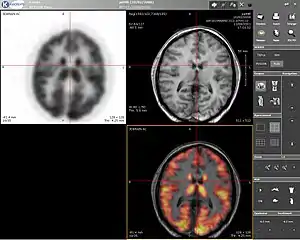

| Computer screenshot showing a PET image (upper left), MRI image (upper right) and the combined PET-MRI image where PET data is overlaid over the MRI data (lower right) | |